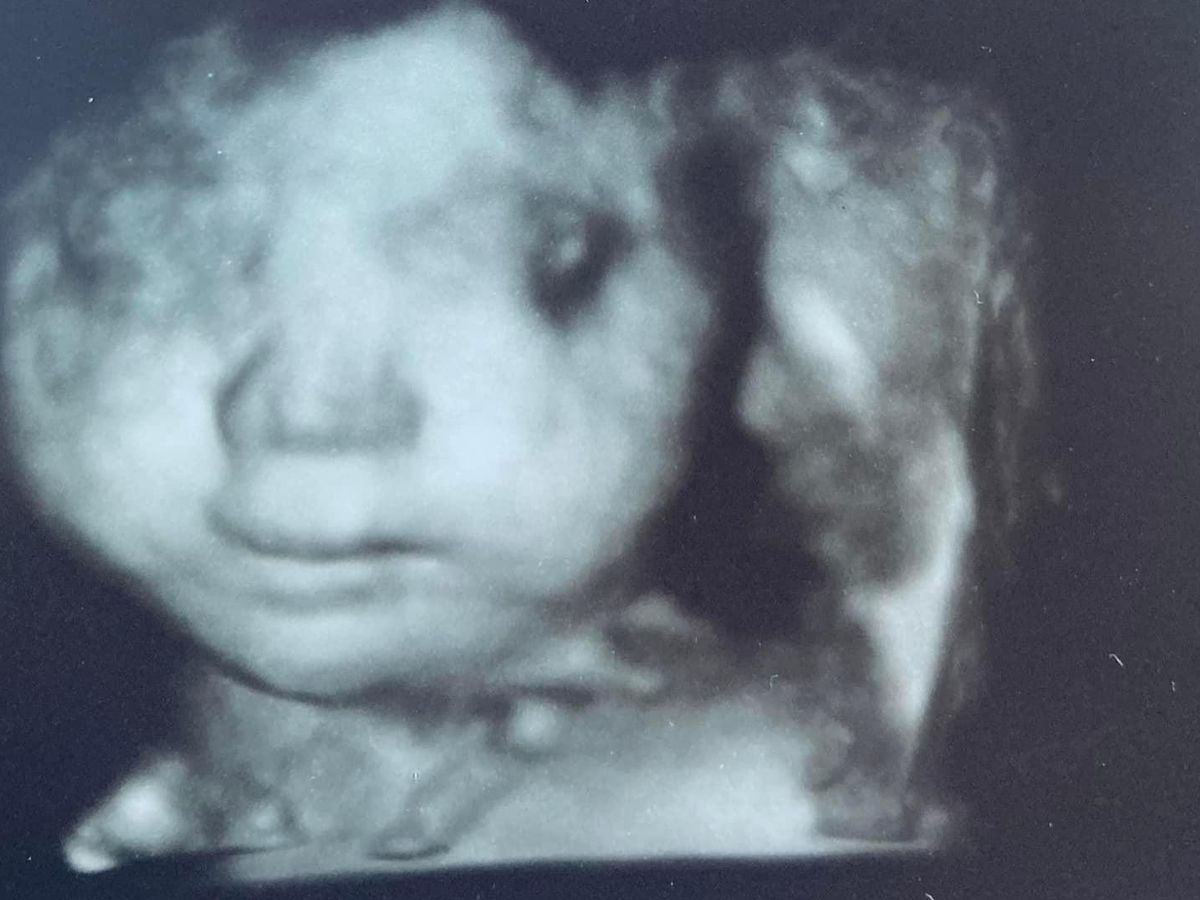

Nikki is an amazing woman, mom and colleague. She was excited to learn she was pregnant with her first daughter (who will be named Jaliyah Nicole), but tragically the baby has trisomy 18. This condition is almost always fatal for the child, who is due in December. Nikki is a single mom to three boys who rely on her, and serves the public by defending individuals from evictions in her job as an attorney.